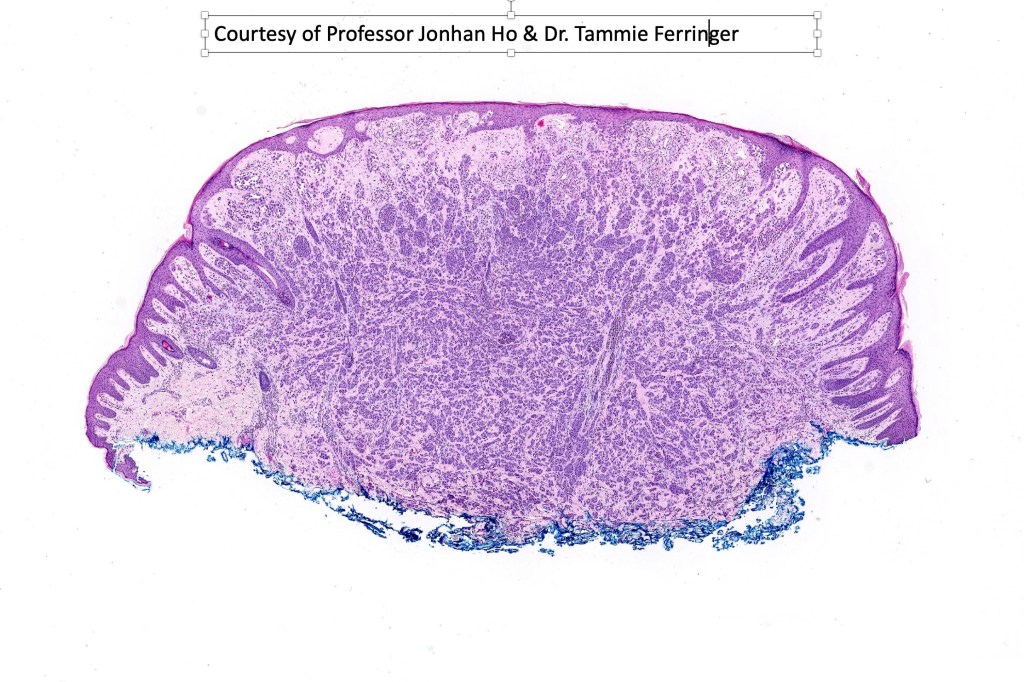

Histological features

•>5-10 mm

•Involve deep dermis or subcutis

•Asymmetrical, poorly circumscribed

•May show effacement/consumption of epidermis or ulceration

•Peripheral Pagetoid spread

•Large nodules which often show impaired maturation